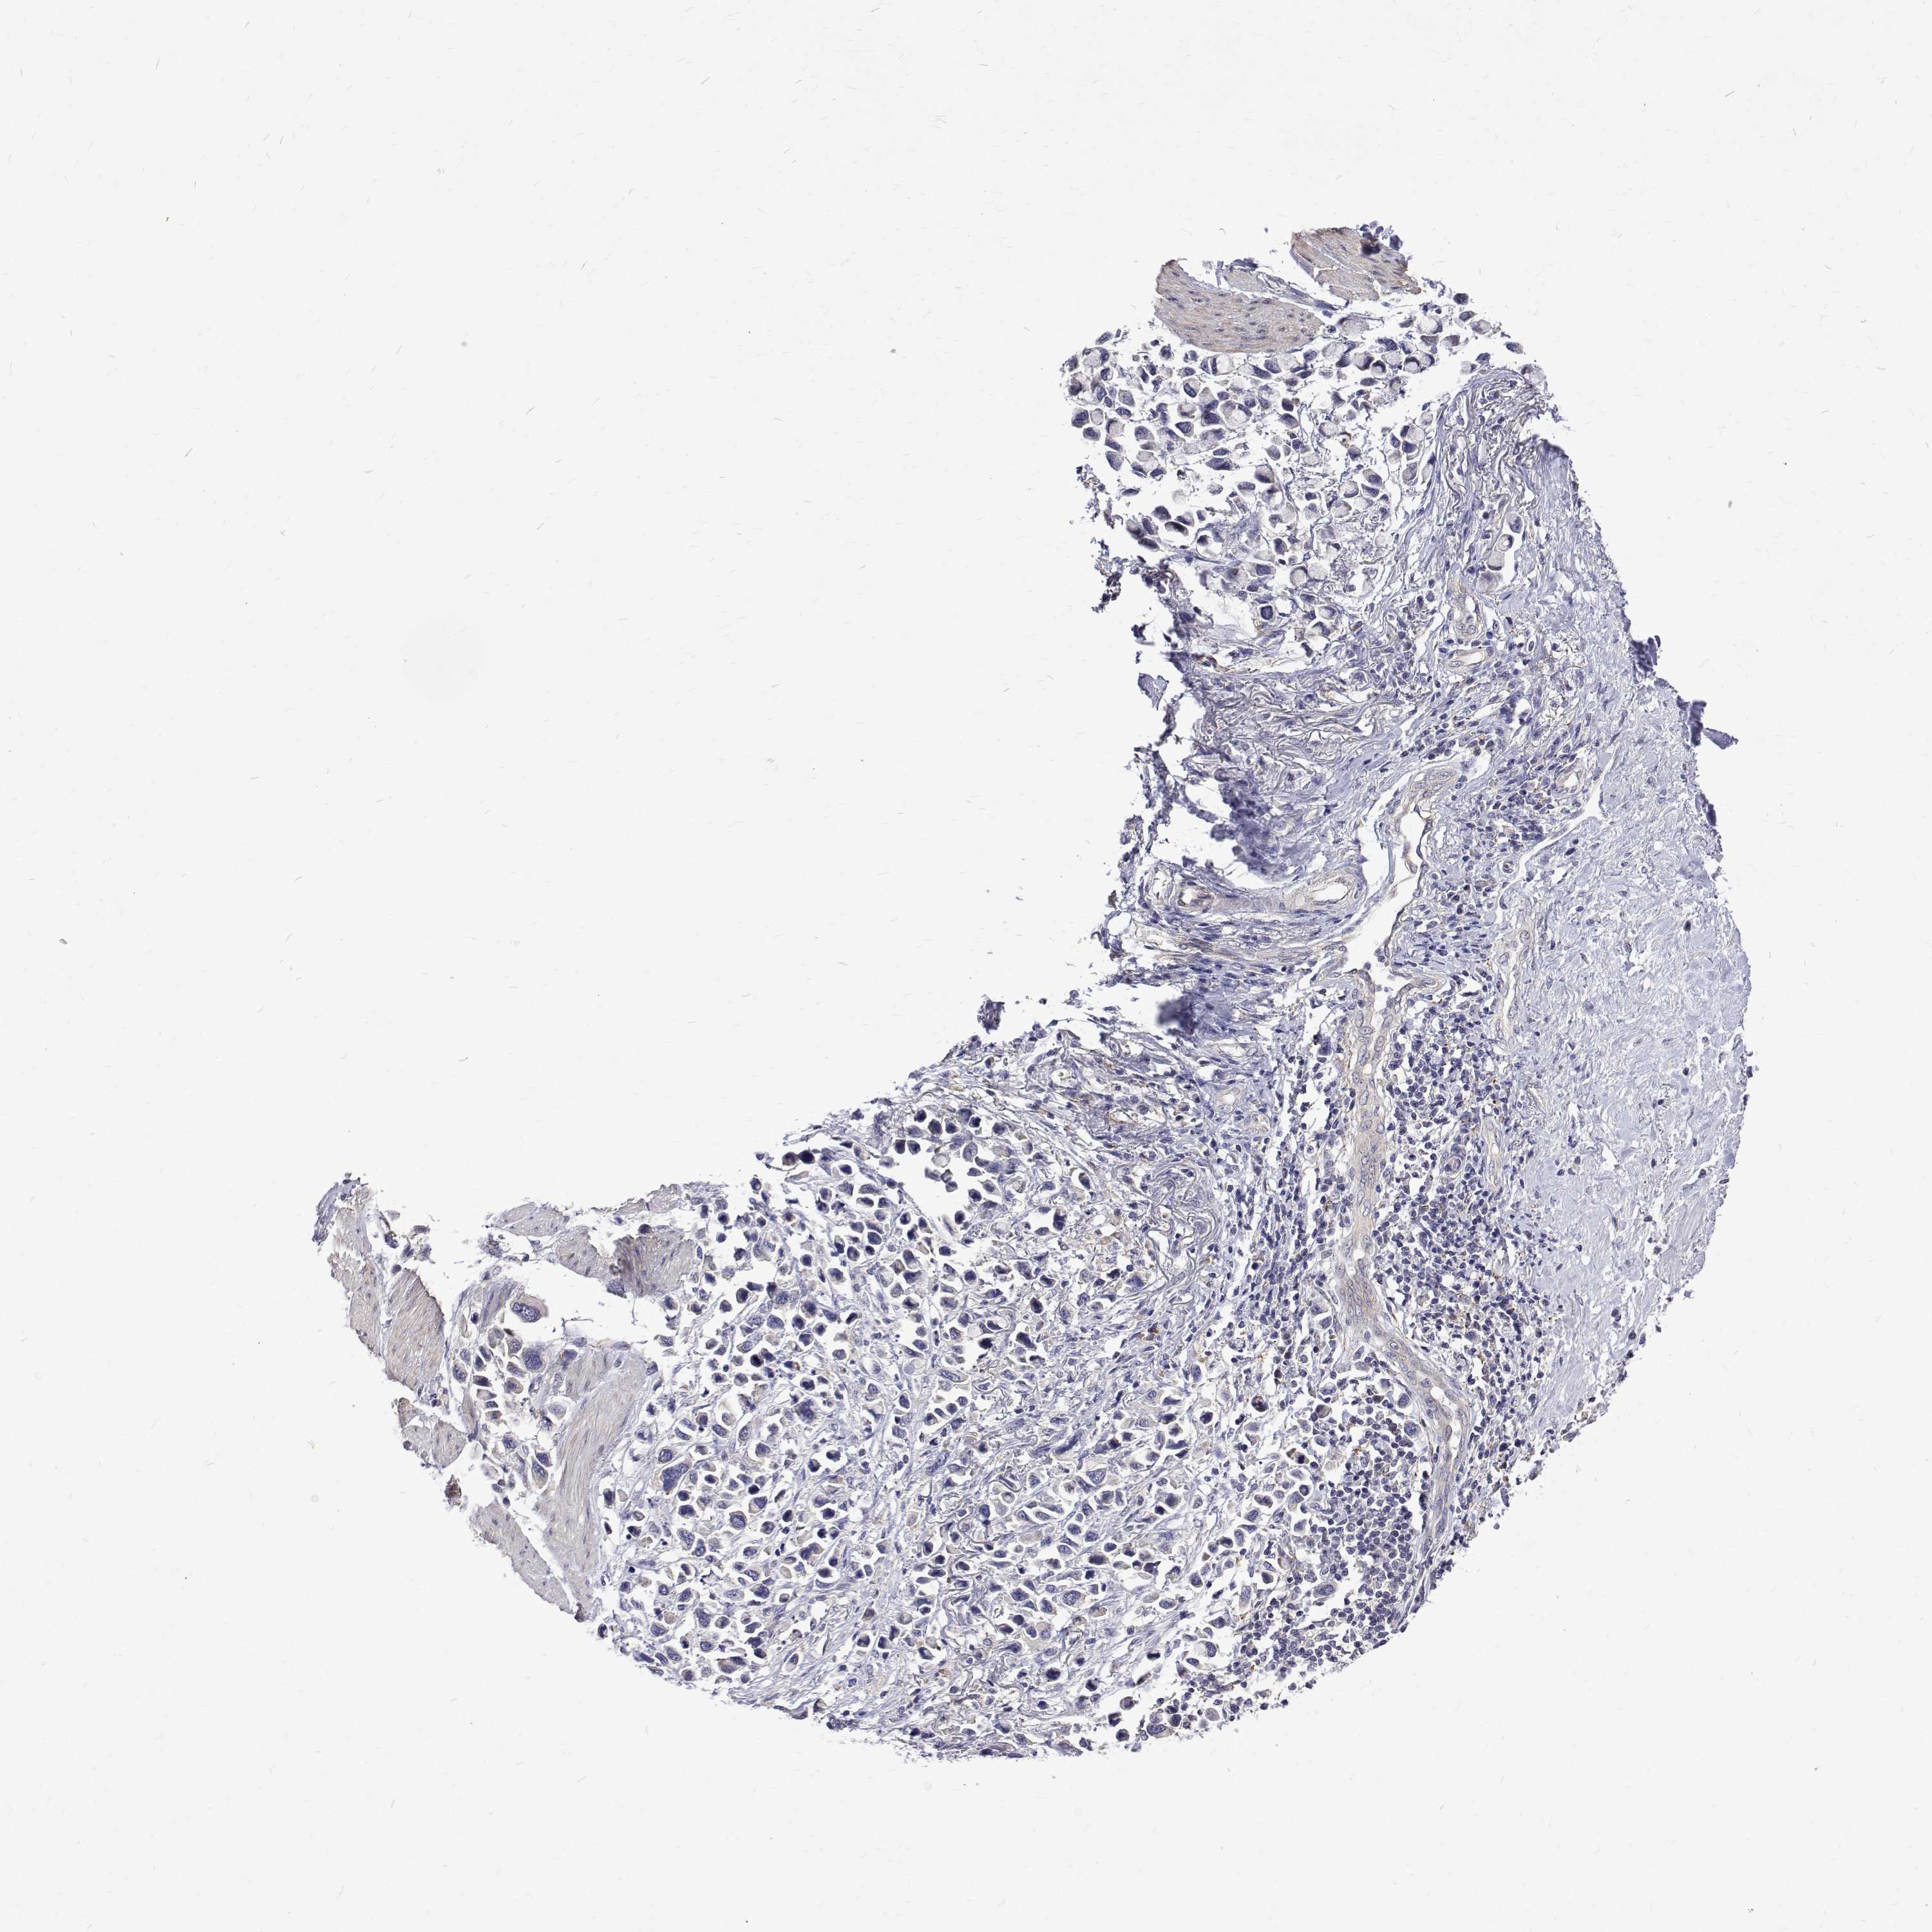

STOMACH CANCER - Protein expressioni

A mouse-over function shows sample information and annotation data. Click on an image to view it in a full screen mode. Samples can be filtered based on level of antibody staining by selecting one or several of the following categories: high, medium, low and not detected. The assay and annotation is described here.

Note that samples used for immunohistochemistry by the Human Protein Atlas do not correspond to samples in the TCGA dataset.

Antibody stainingi

Antibody staining in the annotated cell types in the current human tissue is reported as not detected, low, medium, or high, based on conventional immunohistochemistry profiling in selected tissues. This score is based on the combination of the staining intensity and fraction of stained cells.

Each image is clickable and will lead to virtual microscopy that enables deeper exploration of all samples and also displays staining intensity scores, fraction scores and subcellular localization as well as patient and tissue information for each sample.

Antibody HPA062294

Staining

High

Medium

Low

Not detected

Intensity

Strong

Moderate

Weak

Negative

Quantity

>75%

75%-25%

<25%

None

Location

Nuclear

Cytoplasmic/membranous

Cytoplasmic/membranous,nuclear

Adenocarcinoma, NOS